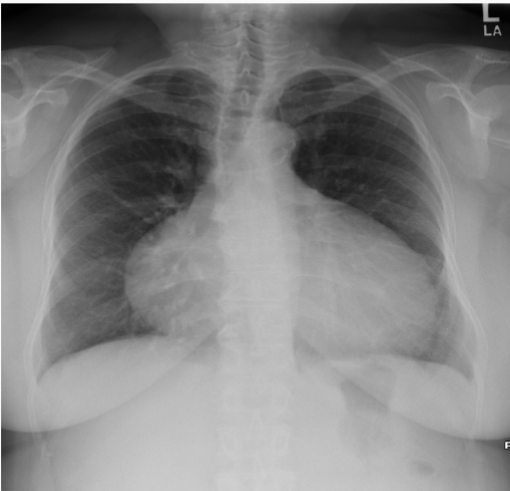

What is this patient presenting with?

Large pericardial effusion-”water bottle sign”